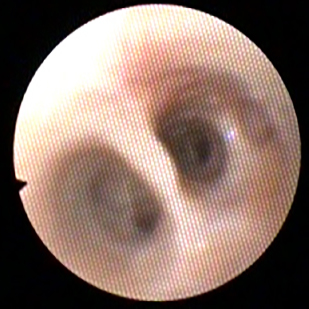

Diagnostiek

Het stellen van een diagnose kan soms net spoorzoeken zijn. Soms is het eenvoudig en soms is het lastig.

Onze diagnostische mogelijkheden hebben we uitgebreid door de aanschaf van vele soorten van apparatuur en het volgen van allerlei cursussen.